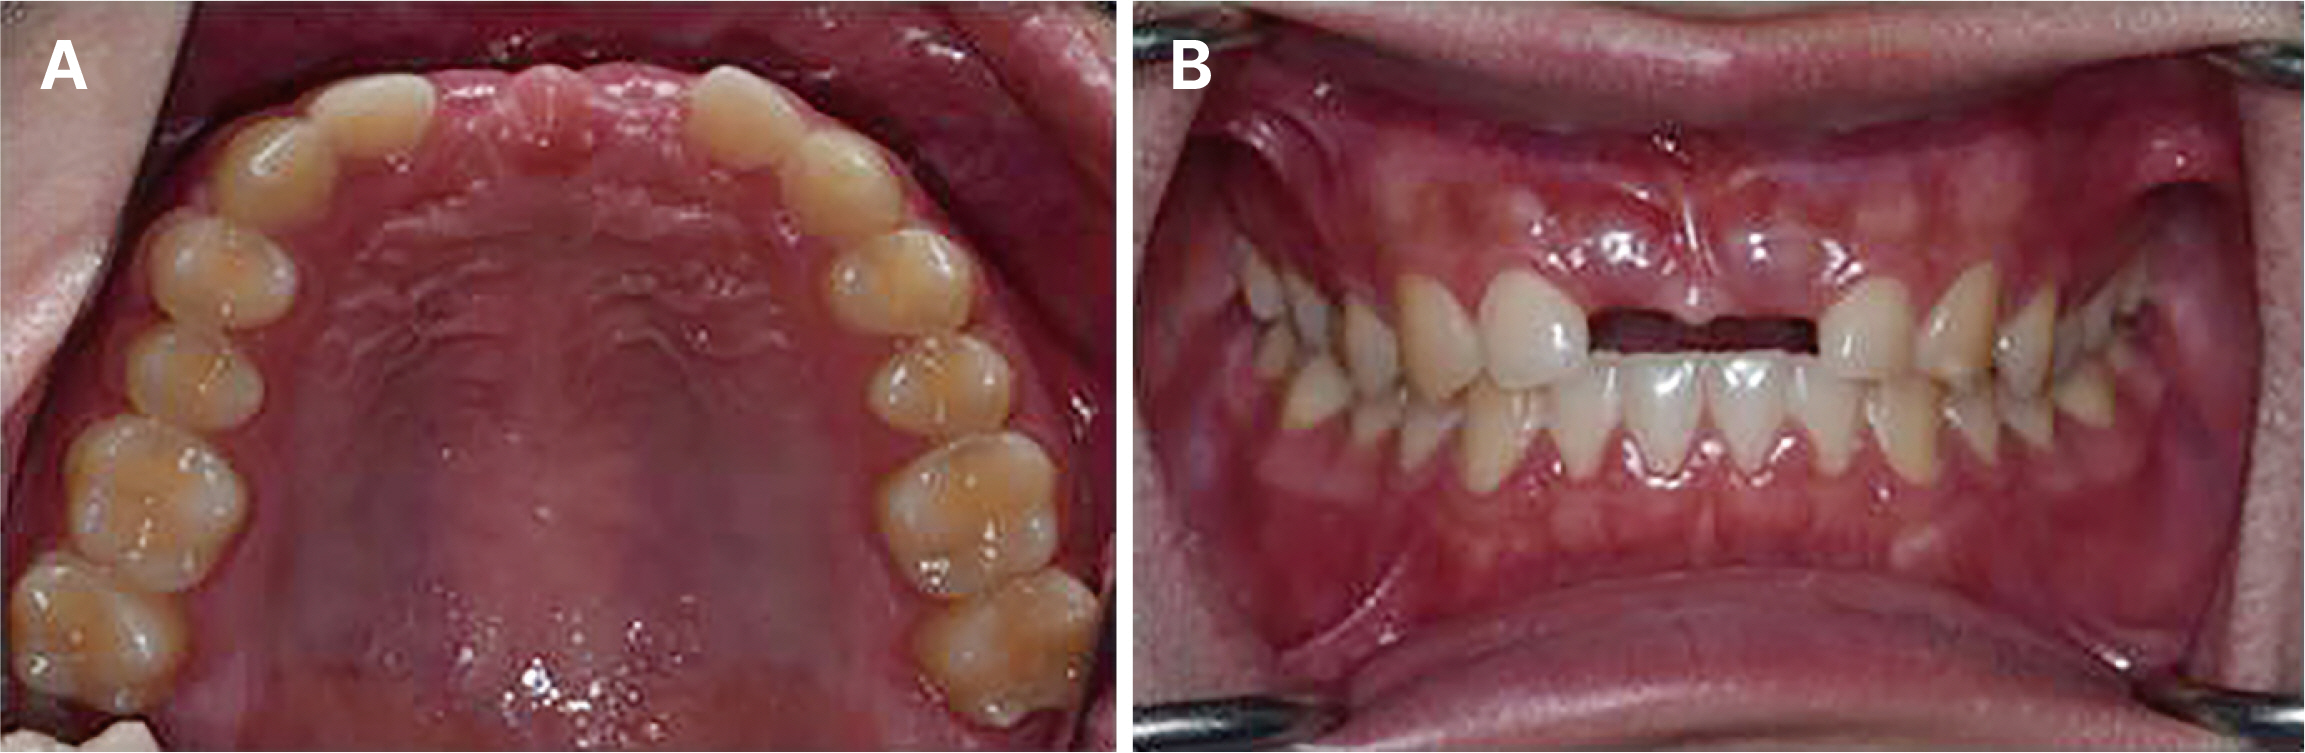

- Immediate implant placement and immediate loading in the anterior maxilla is an effective approach to rapidly address aesthetic demands. To achieve successful outcomes, bone quality, soft tissue condition, and accurate implant positioning are essential factors. For optimal results, procedures such as bone augmentation, precise implant placement, and, when necessary, soft tissue grafting should be considered. Furthermore, provisional restoration play a crucial role in achieving the desired appearance of prosthetic restorations and improving the aesthetics of the soft tissue. By performing soft tissue molding through provisional restoration, an ideal emergence profile can be established, which can be subsequently transferred to the final prosthesis, leading to a functional and aesthetically pleasing restoration. This approach aims to optimize the aesthetic outcomes in the anterior region while preserving the natural contours of the peri-implant soft tissue. In this case, a patient requiring extraction of maxillary anterior tooth underwent immediate implantation and alveolar bone grafting using a guide fabricated in advance from CT data. The patient received a provisional restoration on the same day. Subsequent steps included transitioning from the provisional prosthesis to the definitive prosthesis, ultimately achieving an aesthetically pleasing and functional implant restoration. We report this case to highlight the successful approach to maxillary anterior implant rehabilitation.